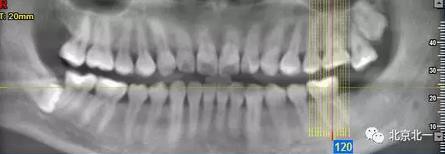

病例資料:一般情況,患者女性,28歲, 主訴:要求拔右側下頜智齒,檢查:右側下頜第三磨牙未見萌出, 拍片如圖。

圖一:CBCT顯示右側下頜水平骨埋伏牙,牙冠距離下牙槽神經(jīng)管接近。

圖二:自帶的CBCT顯示下牙槽神經(jīng)管貼著智齒走形。